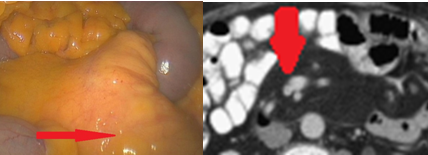

Red arrows — transition point. Multiple air-fluid levels (Courtesy Dr. V. Penopoulos)

The two metastatic foci causing stenosis and bowel obstruction are clearly visible (Courtesy Dr. V. Penopoulos)